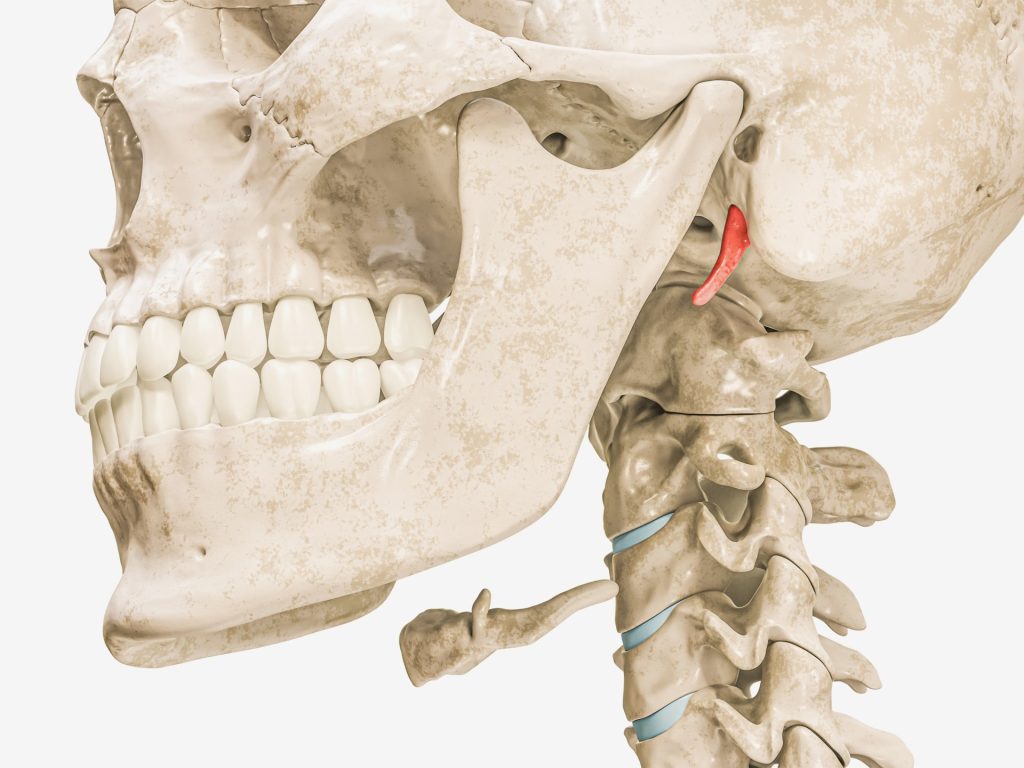

قالت الرابطة المهنية لأطباء الأنف والأذن والحنجرة بألمانيا إن متلازمة إيغل (Eagle syndrome) حالة نادرة تحدث بسبب زيادة طول الزائدة الإبرية (styloid process) الواقعة تحت الأذن مباشرة، أو بسبب نمو العظام في الرباط الإبري اللامي (Ligamentum stylohyoideum) وهو رباط يتصل بالزائدة الإبرية.

وتمت تسمية المتلازمة على اسم طبيب الأنف والأذن والحنجرة الأميركي “وات ويمز إيغل” كونه أول من وصفها، كما تعرف باسم متلازمة ”الإبري اللامي”.